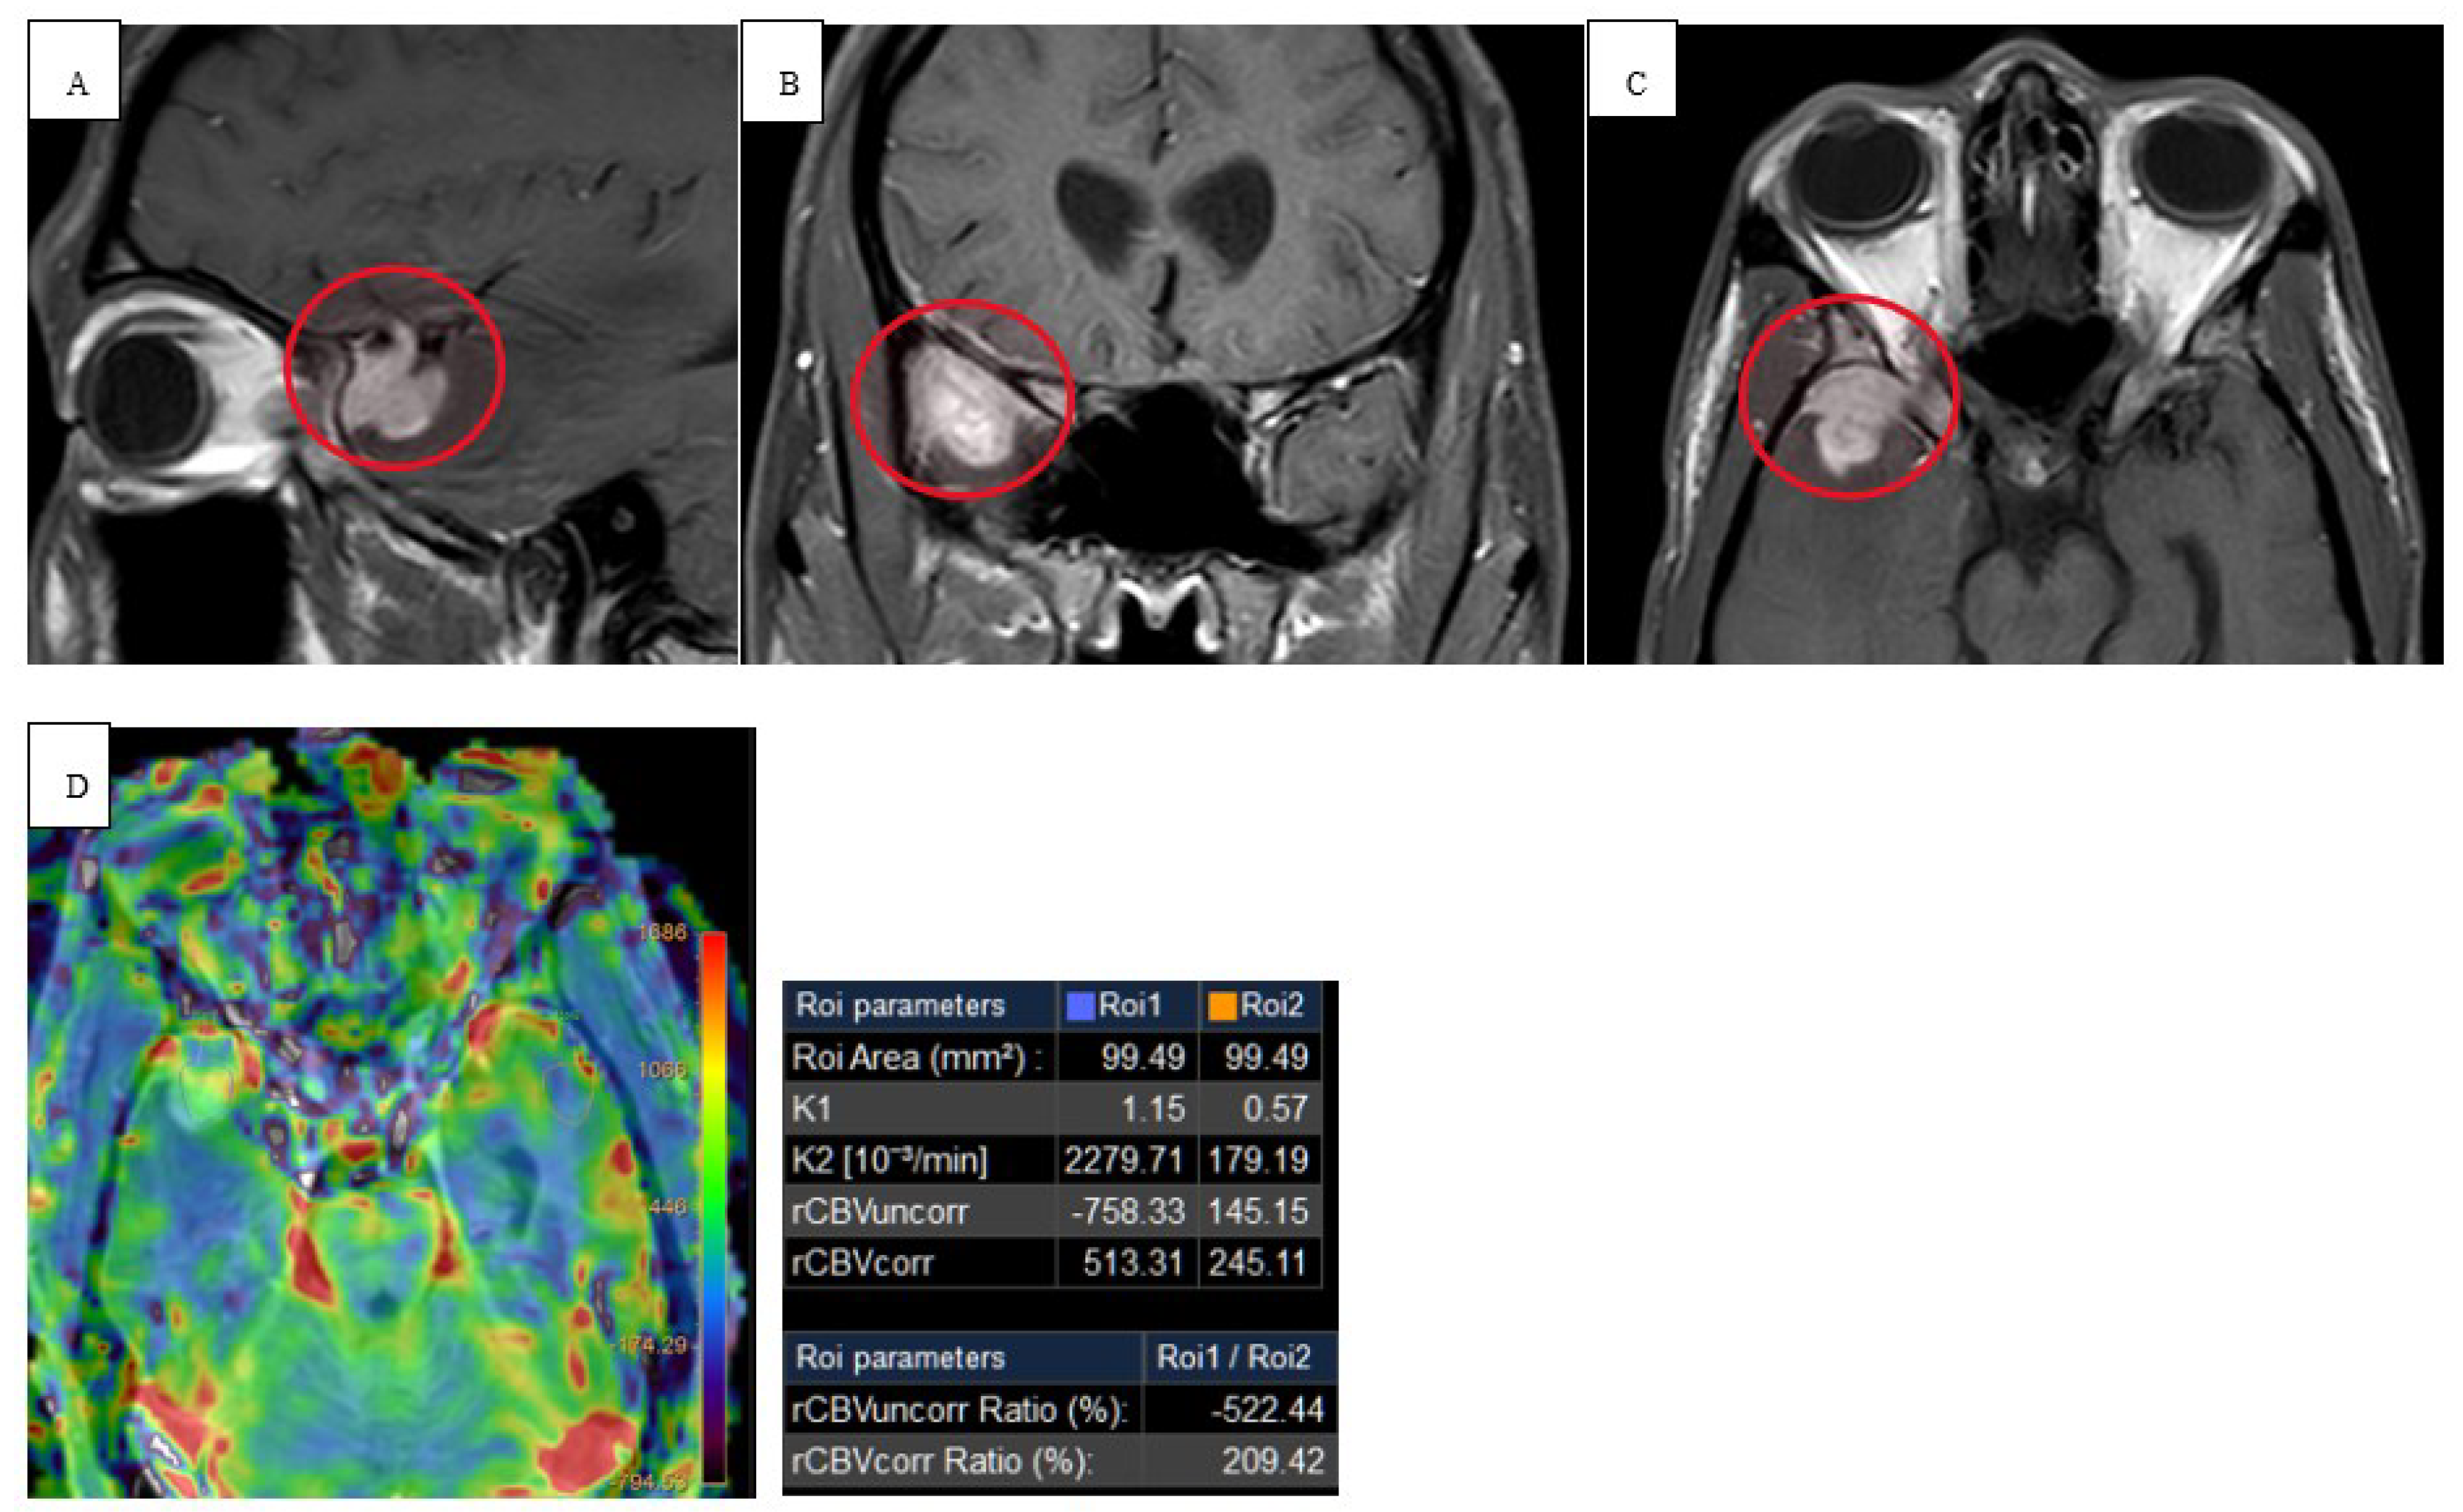

Twenty-eight-year-old female with no significant past medical history except 3 uncomplicated caesarean sections presented for neck swelling. She was found to have persistent cervical lymphadenopathy despite multiple trials of antibiotics. She underwent a right neck excisional lymph node biopsy which revealed cHL and histopathology showcasing interfollicular proliferation of large and multilobulated and single lobe cells with prominent nucleoli consistent with Reed-Sternberg cells. Immunohistochemical staining showed diffuse positivity for CD15/30 with a Ki67 index of 80%. PET-CT neck demonstrated enlarged right neck cervical lymph nodes and MR brain demonstrating characteristic diffusion weighted images (DWI) with apparent diffusion coefficient (ADC) restrictions and T2 FLAIR enhancement within the frontal lobes (Figure 3 and Figure 4). MRI of the chest, abdomen, and pelvis demonstrated right supraclavicular, retroclavicular, infraclavicular, right axillary, and right subpectoral lymph nodes. Initiation of chemotherapy was delayed due to pregnancy; the patient was in her third trimester and opted to start chemotherapy after delivery. During that period, she was monitored clinically. Subsequently, the patient was started on chemotherapy with ABVD (doxorubicin, bleomycin, vinblastine, and dacarbazine). Later, developed neurological symptoms for which brain imaging, CSF evaluation, extensive infectious, and paraneoplastic testing were all negative. The patient had a negative positron emission tomography (PET) CT scan after 2 cycles of chemotherapy. Chemotherapy was continued with omitting bleomycin per The United Kingdom Risk-Adapted Therapy in Hodgkin Lymphoma (RATHL) trial. The patient’s neurological symptoms continued to improve with chemotherapy, and she was in complete remission at the end of chemotherapy. Follow up brain imaging indicated improvement in the leptomeningeal enhancement.

Radiologically, the first-line imaging modality should be a NCCT scan [14,15]. Characteristic findings include a hyperattenuating lesion associated with edema, while immunocompromised patients may have a more heterogenous or even hypoattenuating appearance [14]. MRI reveals iso- to hypointense lesion(s) on T1 weighted scans and iso- to hyperintensity on T2 weighted images [16]. DWI in immunocompetent patients show strong restricted diffusion with low ADC, however, lymphomatous spread in immunocompromised patients is more heterogenous with scattered lesions [17]. In high grade tumors and other metastatic tumors, there is high ADC due to significant vasogenic edema [15]. Our immunocompromised patient in case 1 revealed peripheral restricted diffusion on DWI with T1 isotensity, T2/FLAIR central hyperintensity, and peripheral T2/FLAIR hypotensity (Figure 1 and Figure 2). In a similar sense, case 2 demonstrated restricted diffusion on DWI and low ADC (Figure 3).

Figure 4. Pretreatment post- axial (A) and coronal (B) contrast T1 MRI that demonstrates leptomeningeal enhancement within the bifrontal lobes, predominantly within the parafalcine region. Pretreatment axial pre (C) and post (D) T2 FLAIR contrast enhancement within the bifrontal lobes (orange arrows).